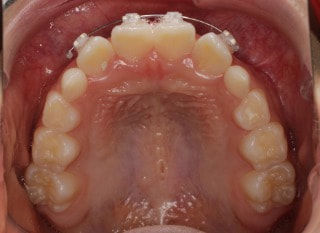

小児期ケース:反対咬合+上顎両側3番埋伏歯

(受け口+右上3番目の永久歯が埋まってしまい、はえてこない)

治療法:上顎急速拡大装置+クリアスナップ+フェイスマスク+上顎右側3番は開窓萌出誘導

治療前